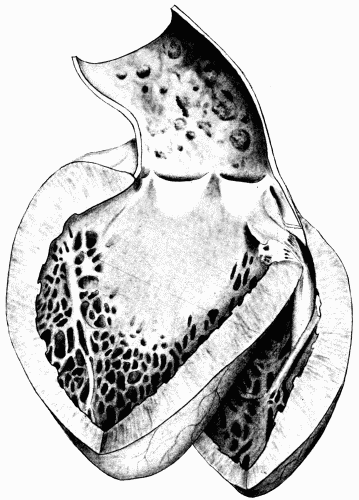

Fig. 3.—Arteriosclerosis of the thoracic and abdominal aorta, showing irregular nodules, atheromatous plaques, denudation of the intima, thin plates of bone scattered throughout with spicules extending into the lumen of the vessel. Note the contraction of the openings of the large branches, the rough appearance of the aorta and the greater degree of sclerosis of the upper two-thirds, i. e., of the aorta above the diaphragm. This aorta in the recent state was much thickened and almost inelastic. Fig. 3.—Arteriosclerosis of the thoracic and abdominal aorta, showing irregular nodules, atheromatous plaques, denudation of the intima, thin plates of bone scattered throughout with spicules extending into the lumen of the vessel. Note the contraction of the openings of the large branches, the rough appearance of the aorta and the greater degree of sclerosis of the upper two-thirds, i. e., of the aorta above the diaphragm. This aorta in the recent state was much thickened and almost inelastic.

Fig. 4.—Arteriosclerosis of the arch of the aorta. Numerous calcified plaques, thickening and curling of the aortic valves, giving rise to insufficiency of the aortic valves. The aortic ring is rigid and not much dilated. (Milwaukee County Hospital.) Fig. 4.—Arteriosclerosis of the arch of the aorta. Numerous calcified plaques, thickening and curling of the aortic valves, giving rise to insufficiency of the aortic valves. The aortic ring is rigid and not much dilated. (Milwaukee County Hospital.)

Fig. 5.—Normal aorta. Compare with Fig. 3. Note the perfectly smooth, glossy appearance of the intima. The openings of all the intercostal arteries are distinctly seen. In the recent state this artery was highly elastic, capable of much stretching both transversely and longitudinally. Fig. 5.—Normal aorta. Compare with Fig. 3. Note the perfectly smooth, glossy appearance of the intima. The openings of all the intercostal arteries are distinctly seen. In the recent state this artery was highly elastic, capable of much stretching both transversely and longitudinally.